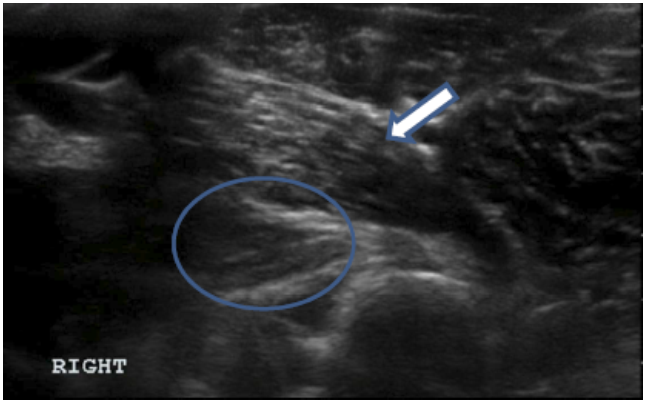

Objective: Iliopsoas injury and strain is a commonly diagnosed disease process, especially amongst working and sporting canines. There has been very little published literature regarding iliopsoas injuries and there is no information regarding the ultrasound evaluation of abnormal iliopsoas muscles. This manuscript is intended to describe the ultrasound findings in 73 canine agility athletes who had physical examination findings consistent with iliopsoas discomfort. The population was chosen given the high incidence of these animals for the development of iliopsoas injury; likely due to repetitive stress.

Methods: Medical records of 73 agility performance canines that underwent musculoskeletal ultrasound evaluation of bilateral iliopsoas muscle groups were retrospectively reviewed. Data included signalment, previous radiographic findings, and ultrasound findings. A 3-tier grading scheme for acute strains was used while the practitioner also evaluated for evidence of chronic injury and bursitis.

Results: The majority of pathologies were localised to the tendon of insertion, with the majority being low grade I-II strains (80.8%). Tendon fibre disruption (71.2%) and indistinct hypoechoic lesions (91.8%) were the most common of acute changes noted. Hyperechoic chronic changes were noted in 84.9 percent of cases. Acute and chronic changes were commonly seen together (62.8%).

Conclusion: Diagnostic musculoskeletal ultrasound was used to identify lesions of the iliopsoas tendon consistent with acute and chronic injury, as well as identifying the region of pathology. The majority of agility performance dogs had low grade acute strains based on the tiered system, with mixed acute and chronic lesions being noted frequently.

Application: Diagnostic musculoskeletal ultrasound provides a non-invasive diagnostic modality for patients suspected of having an iliopsoas strain.